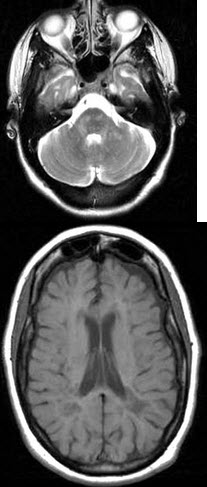

女,40岁,视力下降,请结合CT图像选择最可能的诊断()

[单选题]女,40岁,视力下降,请结合CT图像选择最可能的诊断()A .多发性硬化B .脑出血C .脑梗死D .颅脑外伤E .正常脑实质